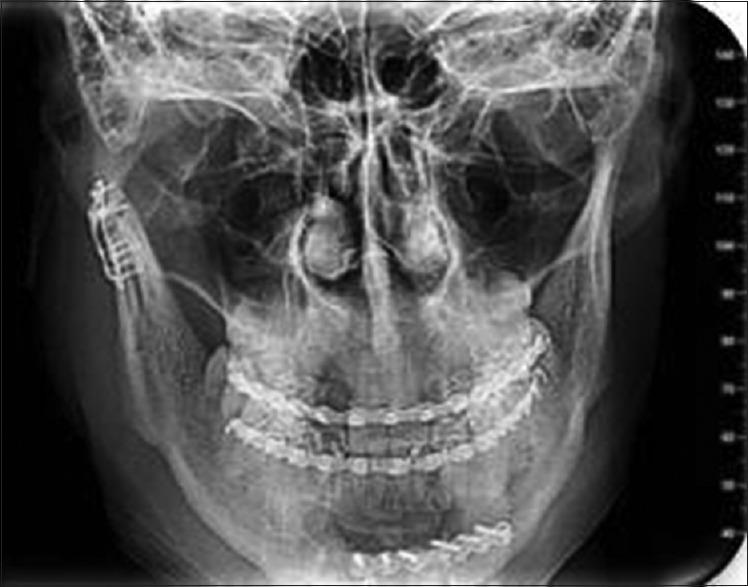

This randomized prospective study was conducted on thirty patients who visited the Department of Oral and Maxillofacial Surgery, Government Dental College, Srinagar, with condylar fractures. All fractures were displaced; either angulated between 10° and 45° and the ascending ramus was shortened by >2 mm to <15 mm. Patients were divided into two groups after satisfying the inclusion and exclusion criteria - Group I (closed treatment) and Group II (open reduction) (15 implants in each group). In Group I, patients were treated by mandibulo-maxillary fixation using arch bar and elastics for 4 weeks, and in Group II, patients were treated by ORIF using two 1.5-mm miniplates. Follow-up was done at 1 month, 3 months, and 6 months. Our postoperative evaluation included five parameters - maximal interincisal opening, protrusion, lateral excursion on fractured and nonfractured sides, anatomical reduction, and pain and malocclusion. Nonparametric data were compared for statistical significance with Chi square test and parametric data with an independent sample's -test ( < 0.05).

Correct anatomical position of the fragments was achieved significantly more accurately in the operative group in contrast to the closed treatment group. Regarding mouth opening/lateral excursion on fractured and nonfractured sides/protrusion, significant ( < 0.05) differences were observed between both groups (open 39.73/7.50/8.17/7.87 mm vs. closed 36.87/6.07/7.23/7.13 mm). Pain also revealed significant ( = 0.025) difference with less pain in the operative treatment group.

本随机前瞻性研究针对30例因髁突骨折就诊于斯利那加政府牙科学院口腔颌面外科的患者开展。所有骨折均有移位;成角10°至45°,升支缩短>2mm至<15mm。满足纳入和排除标准后,患者被分为两组——第一组(闭合治疗)和第二组(切开复位)(每组15例)。第一组患者采用牙弓夹板和弹力牵引进行下颌-上颌固定治疗4周,第二组患者采用两个1.5mm微型钢板进行切开复位内固定术治疗。在1个月、3个月和6个月进行随访。我们的术后评估包括五个参数——最大切牙间开口度、前伸、骨折侧和非骨折侧的侧向运动、解剖复位以及疼痛和咬合紊乱。非参数数据采用卡方检验比较统计学显著性,参数数据采用独立样本t检验(P<0.05)。

与闭合治疗组相比,手术组更显著地实现了骨折块的正确解剖位置。关于骨折侧和非骨折侧的开口度/侧向运动/前伸,两组之间观察到显著(P<0.05)差异(手术组为39.73/7.50/8.17/7.87mm,闭合治疗组为36.87/6.07/7.23/7.13mm)。疼痛方面也显示出显著(P = 0.025)差异,手术治疗组疼痛较轻。